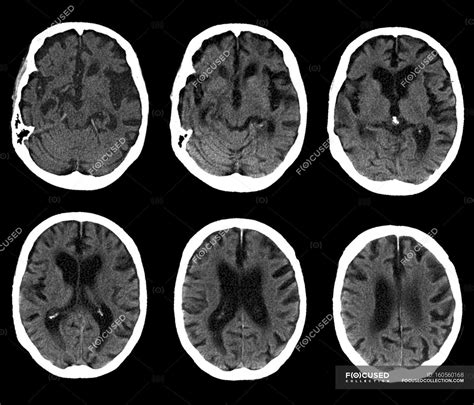

When you or a loved one receives the results of a diagnostic scan, understanding the terminology is crucial for peace of mind. A Normal Brain CT scan is a diagnostic report indicating that radiologists have not found any significant structural abnormalities, masses, or injuries within the brain tissue during the examination. Computed Tomography (CT) scans use X-ray technology to create detailed, cross-sectional images of the head, and receiving a report that defines these images as "normal" is often the primary goal when investigating unexplained symptoms like persistent headaches or dizziness.

A Normal Brain CT refers to a scan where the anatomical structures of the brain appear within the expected range of size, shape, density, and position. Radiologists compare these images against a baseline of what is considered healthy human neuroanatomy. The scan is designed to capture clear visualizations of the brain parenchyma, ventricles, skull, and major blood vessels.

When a radiologist interprets the scan as normal, it means they have systematically checked for the absence of several key conditions, including:

• Intracranial hemorrhages or blood clots.

• Significant brain tumors or masses.

• Signs of increased intracranial pressure.

• Structural abnormalities like aneurysms or malformations.

• Evidence of acute stroke or significant tissue infarction.

It is important to note that a normal report does not always mean there is "nothing wrong." It simply means that the structural integrity of the brain as viewed via CT technology shows no immediate, life-threatening, or obvious physical defects at the time of the scan.